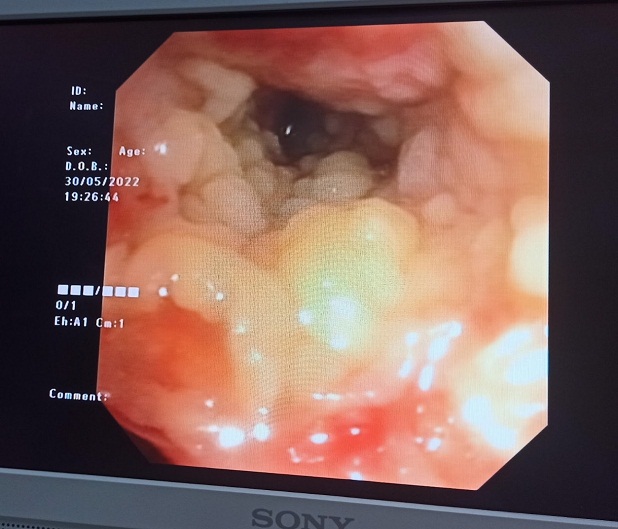

Ngay trong ngày 30/5, bệnh nhân được nội soi phế quản xuất hiện nhiều các mảng giả mạc thùy dưới phổi 2 bên. Với kinh nghiệm điều trị cho nhiều ca phức tạp, các bác sĩ đã nghĩ ngay đến nấm. Và đến ngày 1/6, nội soi phế quản thấy giả mạc phát triển trên toàn bộ niêm mạc đường thở tạo nên các đám sùi và các giả mạc đan xen nhau như mạng nhện lấp kín hết lòng khí phế quản. Ngày 2/6, nội soi thấy các giả mạc bám thành đường thở bong dần ra. Tất cả các mẫu bệnh phẩm đường thở đều có kết quả nhuộm soi ra nấm sợi, kết quả cấy ra Aspergillus fumigatus, hình ảnh giải phẫu bệnh giả mạc ra Aspergillus fumigatus tập trung nhiều thành đám.

Hình ảnh soi phế quản ngày 30/5: xuất hiện giả mạc thùy dưới phổi 2 bên